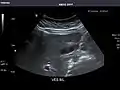

- Right kidney

Kidneys: Right and left kidneys measure 11.5 cm and 12 cm in length respectively. No hydronephrosis. Small left lower pole kidney cyst.